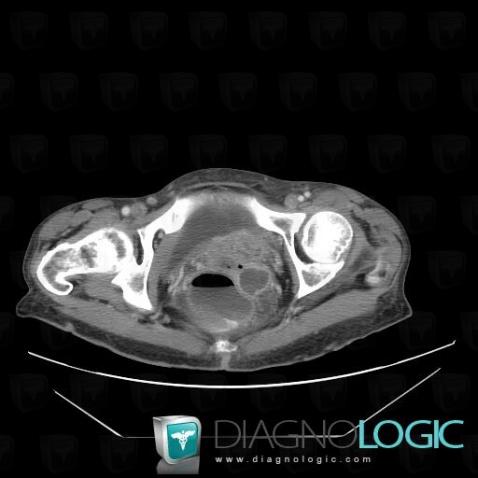

Voici les informations spécifiques à l'image clé ci dessus:

- Diagnostic Métastase, Localisation(s) Pelvis / Périnée, comportant les gammes Masse pelvienne kystique